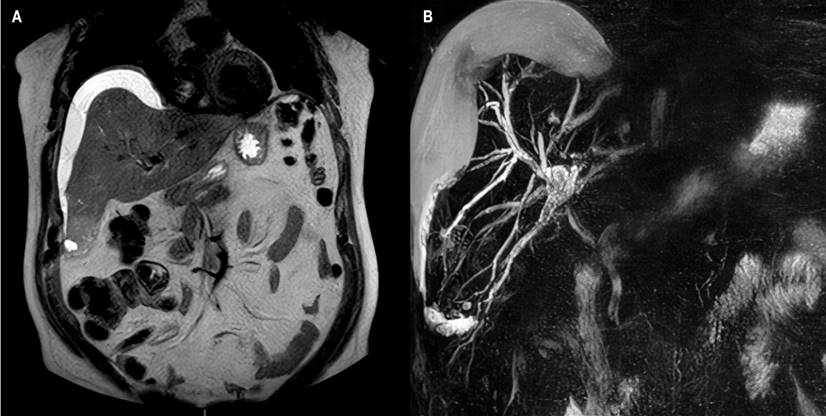

Se tomó una ecografía abdominal en la que se describió dilatación de la vía biliar con la medición de la vía derecha: 5 mm, la izquierda: 4,8 mm y en la confluencia: 5,3 mm. También se describió una escasa cantidad de gas a nivel de las vías biliares intrahepáticas. Se tomó una colangiorresonancia con hallazgo de alteración focal en la región subcapsular del segmento VI hepático con imagen de 34 x 31 x 37 mm, de contenido heterogéneo e imágenes similares de menor tamaño, 10 y 13 mm, en el segmento VIII, sospechosas de abscesos; se documentó también líquido subcapsular hepático en el lóbulo derecho (112 mL) (Figura 1) y dilatación de la vía biliar intrahepática con imágenes de microlitiasis en el conducto hepático derecho cerca a la confluencia y en el segmento intrapancreático del conducto colédoco. Pasadas 48 horas se realizó una resonancia magnética de abdomen con hallazgo de aumento del volumen de la colección subcapsular hepática (Figura 2), por lo que el paciente fue llevado a inserción de un catéter multipropósito. En el procedimiento se realizó un drenaje de 1600 mL de líquido de aspecto biliar purulento. El paciente continuó por 5 días con drenaje biliar de 350-500 mL diarios por el catéter multipropósito y con signos de respuesta inflamaría, por lo que fue llevado a CPRE.

Figura 1 Colangiorresonancia. A. En secuencia T2, colección subcapsular: bilioma. B. Reconstrucción 3D de la vía biliar. Archivo de Imágenes del Hospital Universitario Hernando Moncaleano Perdomo de Neiva.